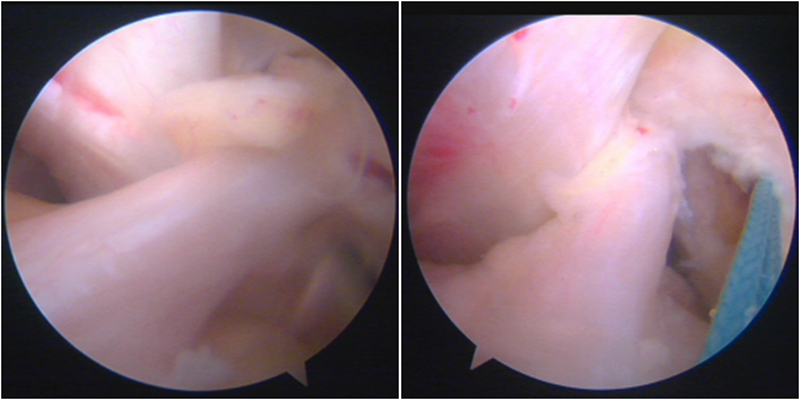

送止血带后韧带表明血管膜